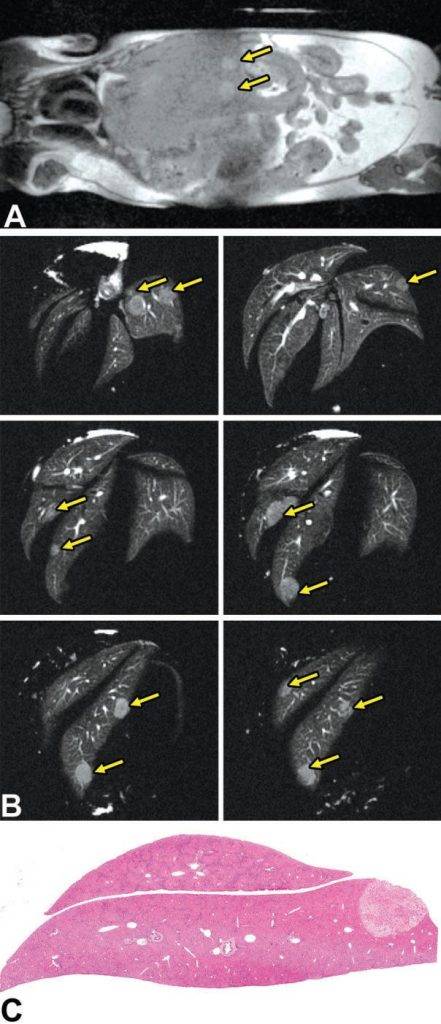

活體磁共振成像在模型小鼠中檢測到局灶性肝損傷(圖A)。肝臟的高分辨率離體MRH評估可以在小鼠(圖B和C)中鑒定幾個單獨(dú)的局灶性脂肪病變。通過常規(guī)組織病理學(xué)證實(shí)病變?yōu)榫衷钚灾靖淖儯▓DC)。